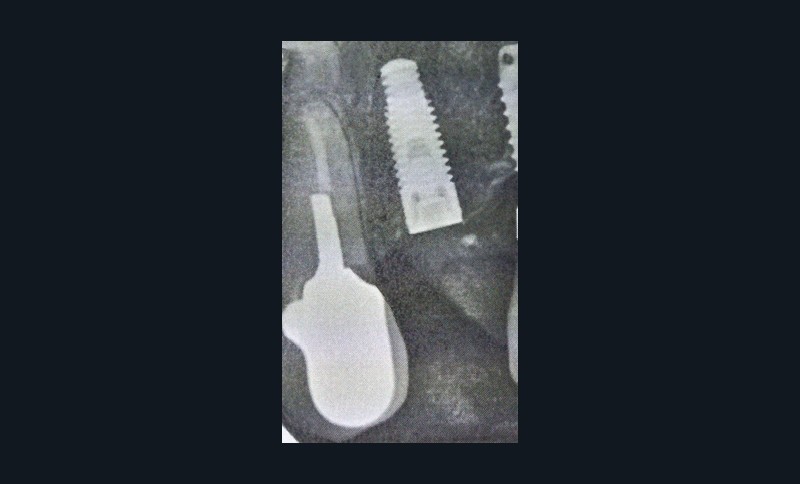

Le nombre de patients traités pour l’ostéoporose notamment est important parmi la patientèle des cabinets dentaires. La question sur la possibilité de pose d’implants est récurrente chez ces patients. Ainsi, il est important de rappeler qu’il faudra systématiquement rechercher la prise éventuelle d’IRO au cours de l’interrogatoire médical. Les patients ne faisant pas toujours le lien avec nos gestes pourront omettre de le signaler spontanément.

Si les recommandations et les différents auteurs s’accordent depuis longtemps pour contre-indiquer la pose d’implant dans le contexte malin, celle-ci n’est pas contre-indiquée chez un patient traité par IRO dans un contexte bénin [9]. De nombreuses publications ont montré des taux de succès comparables à ceux de la population générale. Cependant, ces données sont à considérer avec discernement car le recul et le niveau de preuve scientifique sont encore faibles [10]. Ainsi, il semble raisonnable de ne pas réfuter de principe la solution implantaire chez ces patients. Mais il conviendra de les informer clairement du rapport bénéfice/risque. Trois points semblent indispensables pour aider à la décision. Il s’agira d’évaluer la durée du traitement (plus ou moins 3 années), les facteurs de comorbidité (diabète, corticothérapie notamment) et l’invasivité du geste chirurgical (implant unitaire ou multiple, nombre de sextants concernés) (fig. 3). Dans tous les cas, les alternatives thérapeutiques devront être proposées et discutées avec le patient.